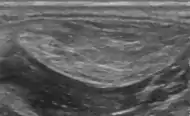

A physical exam is typically the easiest way to diagnose it. Rarely, a tissue biopsy or imaging may be required. The imaging modality of choice is magnetic resonance imaging (MRI) because it has superior sensitivity of distinguishing it from liposarcoma as well as mapping the surrounding anatomy.[22]

A lipoma is a benign tumor made of fat tissue.[1] They are generally soft to the touch, movable, and painless.[1] They usually occur just under the skin, but occasionally may be deeper.[1] Most are less than 5 cm (2.0 in) in size.[2] Common locations include upper back, shoulders, and abdomen.[4] It is possible to have a number of lipomas.[3]

The cause is generally unclear.[1] Risk factors include family history, obesity, and lack of exercise.[1][3] Diagnosis is typically based on a physical exam.[1] Occasionally medical imaging or tissue biopsy is used to confirm the diagnosis.[1]